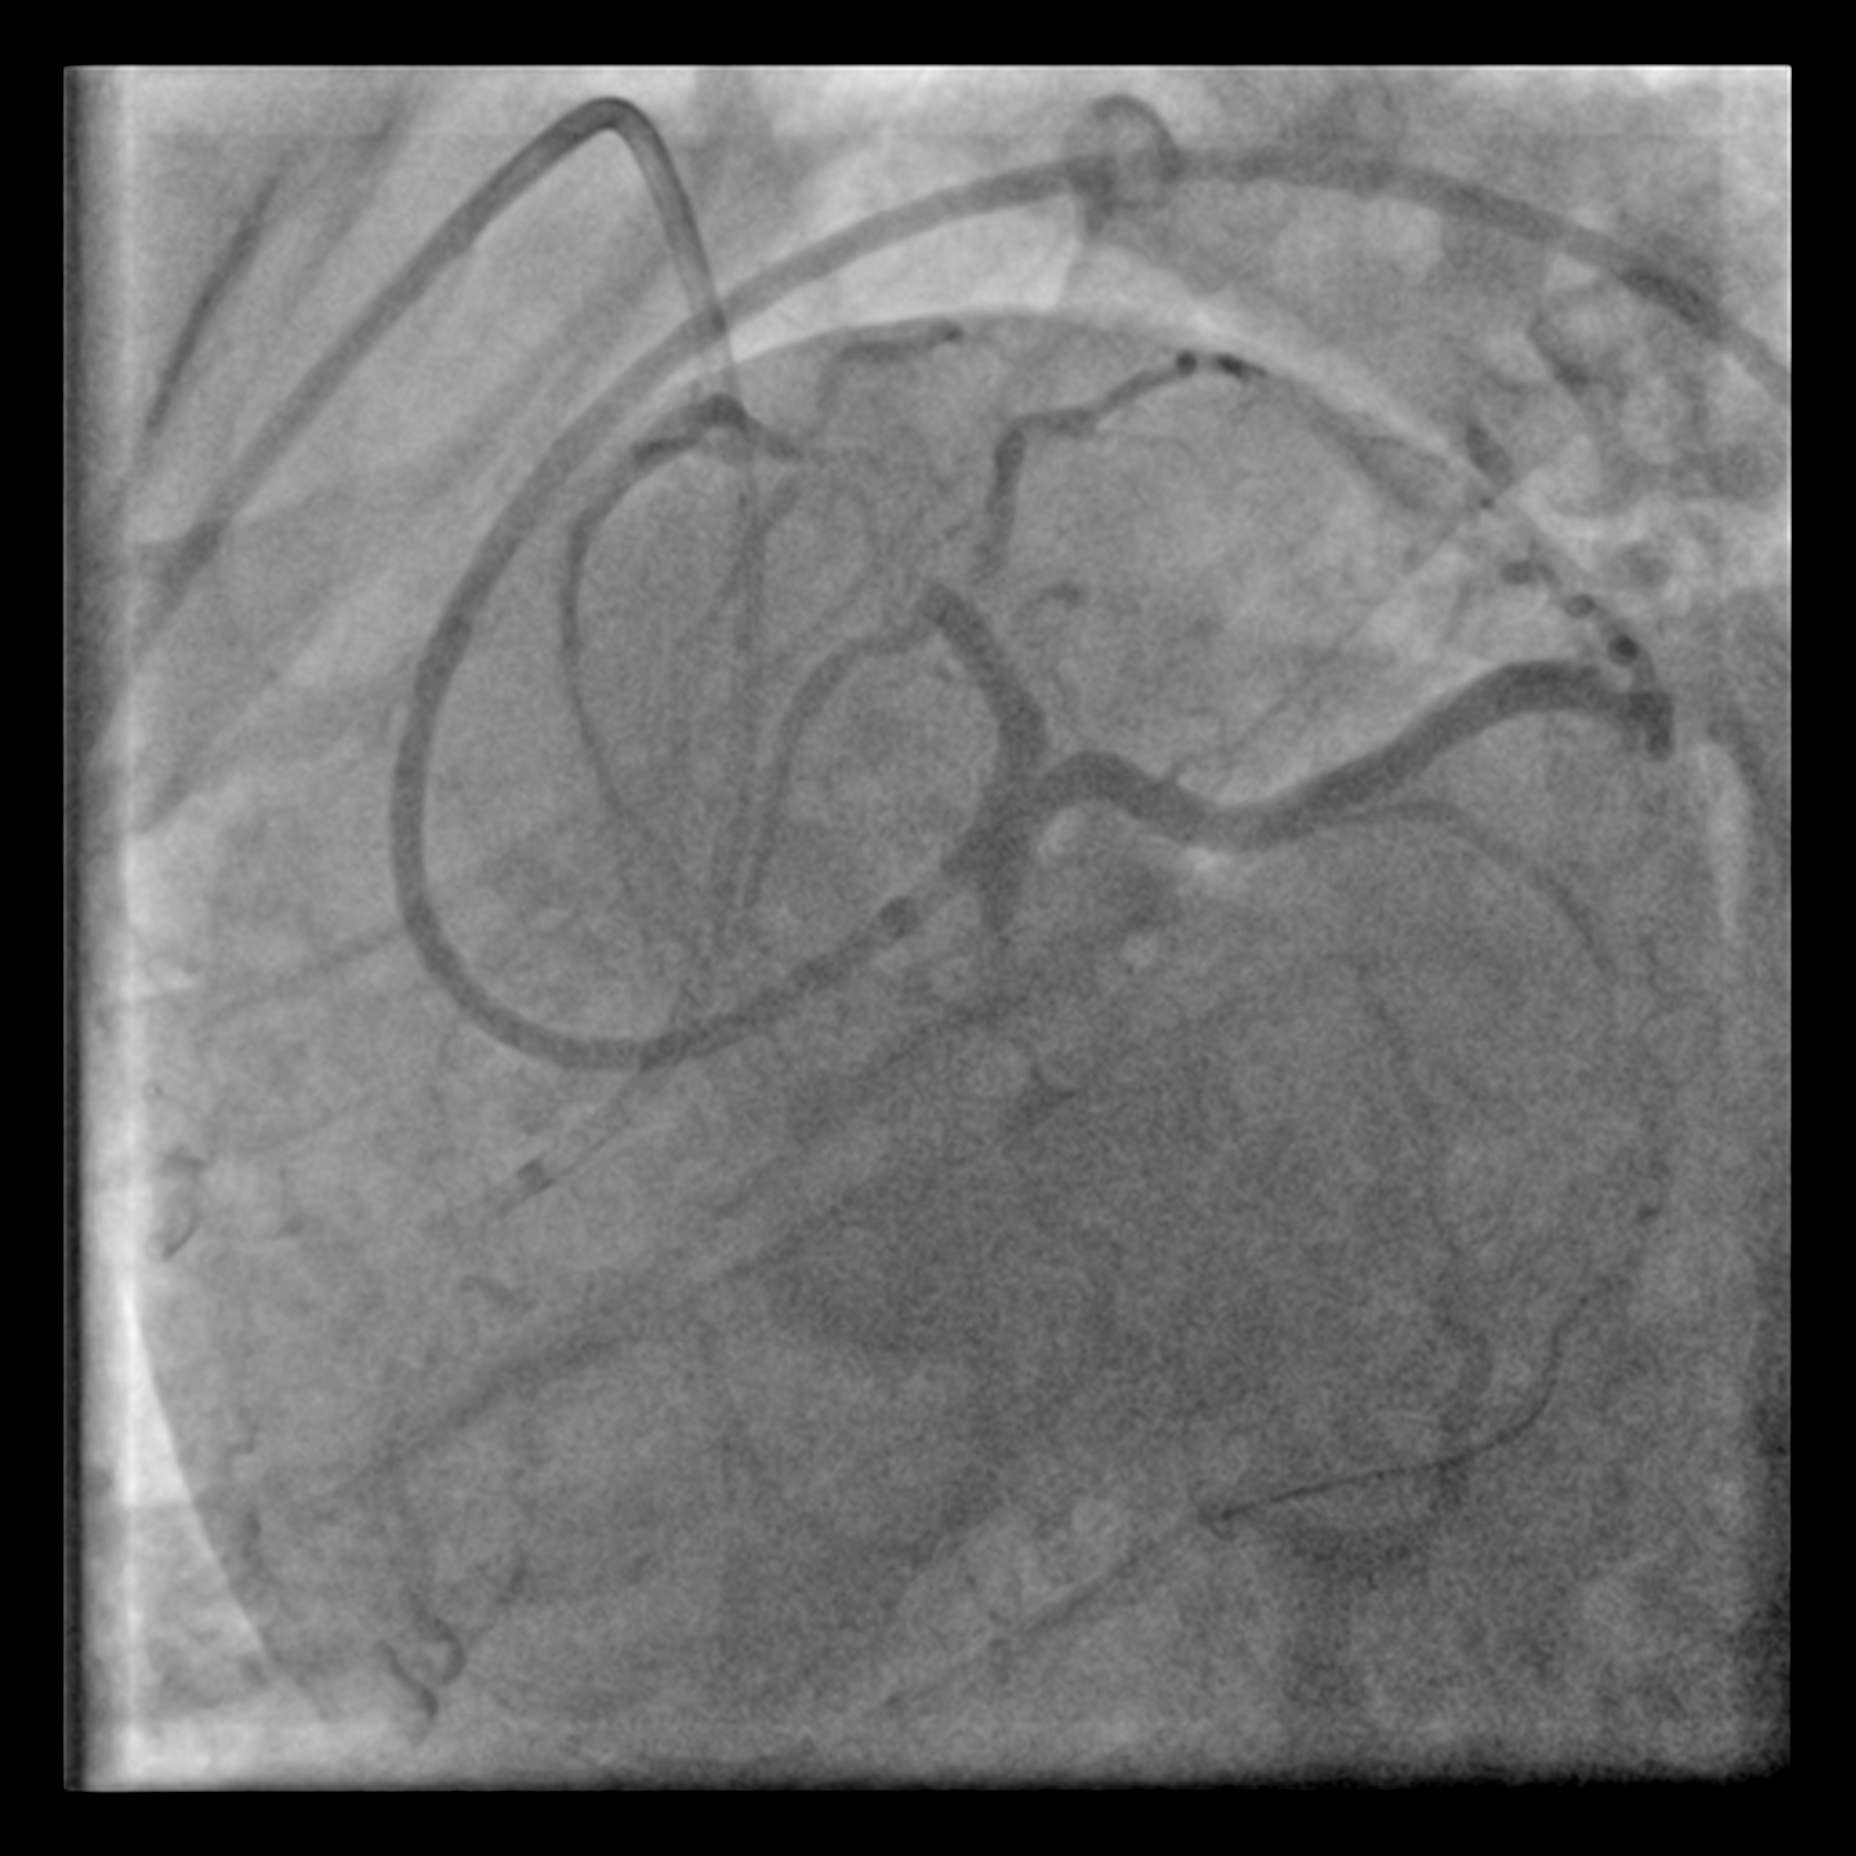

The proximal LAD demonstrates a Chronic Total Occlusion (CTO) with collateral flow from the Right Coronary Artery (RCA) via a septal perforator. The J-CTO score is 2, attributed to a blunt proximal cap and an estimated lesion length of more than 20 mm. The indication for CTO intervention is angina refractory to medical therapy. The procedure was planned using an antegrade approach via a 7 Fr EBU 3.5 catheter, with a contralateral injection from the RCA for visualisation.

With the support of a FineCross micro-catheter (MC), the proximal CTO cap was punctured with a Gaia First wire. The wire traversed the CTO body through the intra-plaque space without much difficulty, reaching the distal lumen, which was confirmed by contralateral injection. However, the MC could not be delivered to the distal lumen over the Gaia First wire. The CTO lesion was pre-dilated with a 1.0 mm balloon, but it burst during the fourth inflation, and the MC still failed to advance. Subsequently, a trapped foreign body was noted on the distal aspect of the wire that prevented the advancement of the MC. This was initially thought to be a fragment fractured from the 1.0 mm balloon. The intervention was continued over the Gaia First wire to facilitate the removal of the fragment. The lesion was pre-dilated with a 2.5 mm non-compliant (NC) balloon and a 3.5 mm cutting balloon. Two 3.5 mm drug-coated balloons (DCBs) were then used to treat the lesion. With adequate luminal gain, an extension catheter was advanced into the LAD, and the fragment was retrieved inside it. A 1.5 mm balloon was then deployed to trap the fragment inside the extension catheter. The wire, extension catheter, and inflated 1.5 mm balloon were then removed simultaneously from the LAD. Inspection of the wire revealed that the fragment was, in fact, an unraveled coronary wire rather than a fractured balloon.